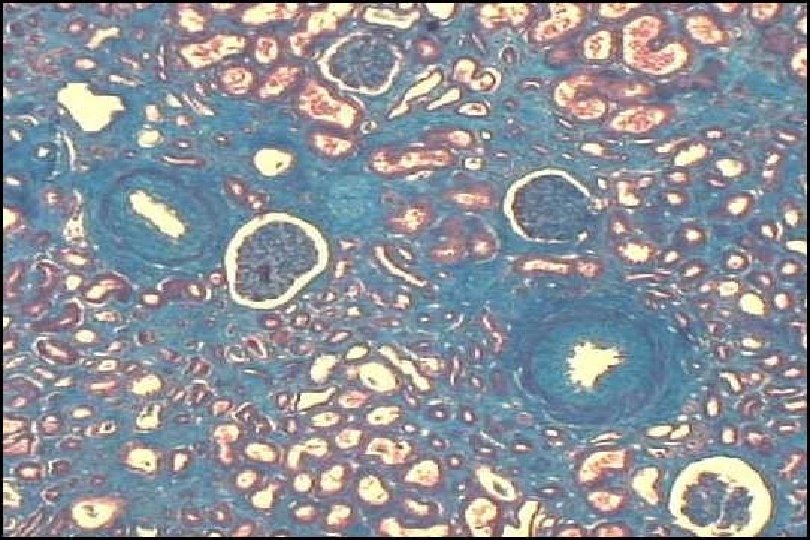

Sirius red derived VInt. Fib and time to graft failure Grimm PC et al, J Am Soc Nephrol 2003